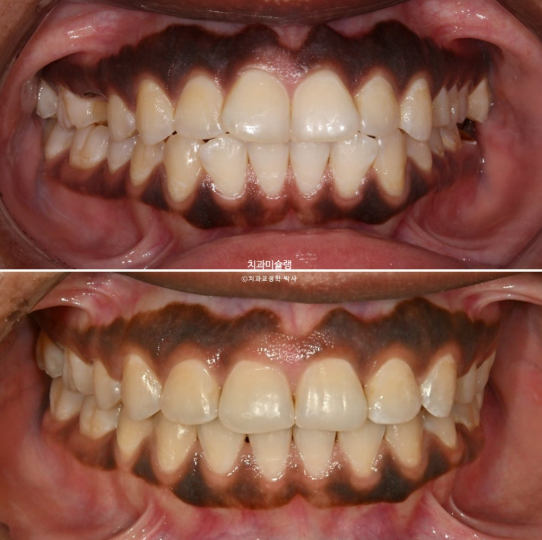

The maxillary and mandibular midlines are well aligned,

and the molar occlusion demonstrates a tight Class I relationship with no spacing.We will now review the before-and-after comparison.

2023.07-2025.12

The treatment, including implant placement, was completed with a clean and stable result.

The patient’s broad smile, showing even the second molars, is particularly attractive. This type of “big smile” is relatively uncommon among Asian patients.

With the protruded anterior teeth corrected, the smile appears much more refined and harmonious.